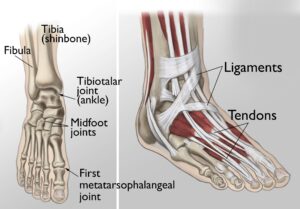

The foot and ankle play a critical role in supporting the body during standing, walking, and running. They provide balance, absorb shock, and facilitate movement. The ankle joint consists of three primary bones that enable up-and-down motion, while the foot comprises 28 bones and over 30 joints, allowing a broad range of movements.

Many of these joints are protected by articular cartilage, a smooth, slippery tissue that ensures seamless movement by allowing bones to glide over one another. Surrounding the joints is the synovium, a thin membrane responsible for producing lubricating fluid that minimizes friction during movement.

Ligaments, which are tough bands of tissue, connect the bones and stabilize the joints. Meanwhile, muscles and tendons provide the strength and support needed for mobility.

(Left) The joints of the ankle, midfoot, and big toe are commonly affected by arthritis. (Right) Ligaments connect the bones to each other, and tendons connect the bones to the surrounding muscles of the lower leg.